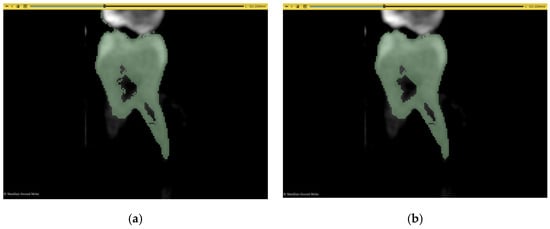

2.6. Workflow 3: WS

2.7. Workflow 4: Automated DentalSegmentator